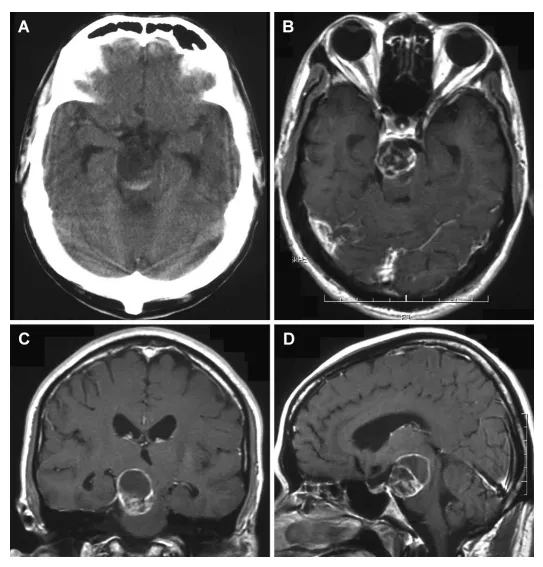

42岁男性因左侧偏瘫2周入院。头颅磁共振显示脑干旁异常病灶。体格检查见左侧轻偏瘫(徒手肌力测试4/5级),颅神经检查显示右侧滑车神经麻痹及三叉神经第三支分布区感觉减退。全身系统检查无异常,无神经纤维瘤病皮肤表现。MRI显示脑外占位性病变,T1加权像呈低信号,T2加权像呈高信号,增强扫描见脚间池内边界清晰的强化多囊性病灶,压迫脑干,肿瘤直径2.5厘米。患者出院后拟2个月后手术。

1个月后因左侧偏瘫加重急诊再入院。颅神经检查显示左侧偏瘫加重至2/5级,合并右侧动眼神经麻痹、滑车神经麻痹、三叉神经全分布区感觉减退及面瘫。CT及MRI显示肿瘤内出血,直径扩大至3.0厘米。

A:平扫CT显示低密度肿块伴高密度区域,提示瘤内出血;

B:轴位图像;

C:冠状位图像;

D:矢状位T1加权增强MRI,可见脚间池内边界清晰的强化多囊性病灶,压迫脑干。